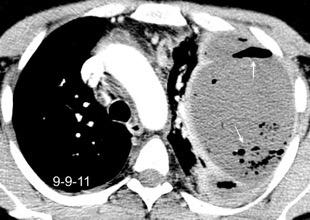

Absceso secundario a perforación de carcinoma. 3-4%. En flexura esplénica puede tener absceso subfrénico o empiema.

Empiema pleural secundario a carcinoma de la flexura esplénica (masa visible)

Lian R et al. Empyema caused by a colopleural fistula. Medicine (Baltimore) 2017/Osada T,, et al. Thoracic empyema associated with recurrent colon cancer: report of a case and review of the literature. Dis Colon Rectum 2001